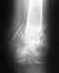

Re: Открытый перелом обеих костей голени 27 лет, Таиланд, необходима консультация

Операцию, конечно, лучше сделать. Вопрос - когда лучше. Тут определенного одного ответа нет. Можно оперировать было как закрытый перелом. Можно и подождать заживления раны. Можно и оперировать как открытый перелом, в два этапа - санчала аппарат, а после заживления раны - внутренняя фиксация.